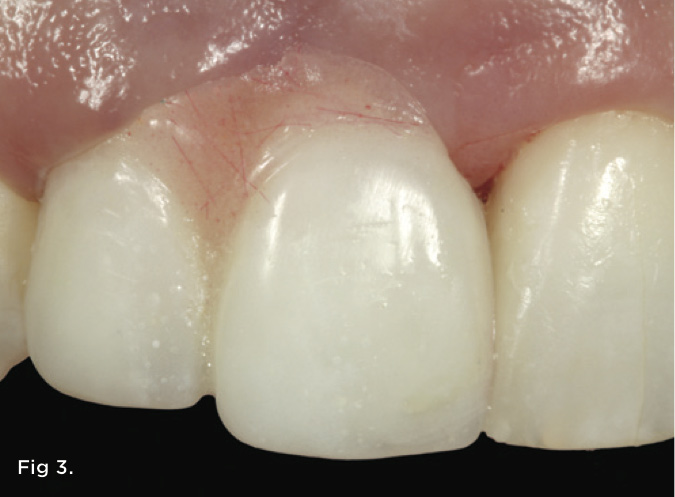

A 38-year-old Caucasian female patient presented with a high smile line and loss of the papilla between tooth No. 7 and edentulous adjacent site No. 8 (Figure 1). Understandably, the patient was unhappy and embarrassed about her esthetic condition. Her dental history revealed tooth replacement of No. 8 with an implant that eventually failed. The site had been previously bone grafted upon implant removal. She was given a composite pontic No. 8 bonded to a tooth No. 7 composite veneer as a transitional restoration. The implant was positioned too close to the proximal surface of tooth No. 7, which stripped the periodontal attachment of the root and ultimately caused loss of the papilla (Figure 2). As previously outlined, the treatment sequence would be to first provide a provisional restorative solution to evaluate the projected outcomes and assess if the patient was willing to undergo orthodontic therapy. In this situation, a full-coverage crown No. 7 with a cantilevered pontic No. 8, with artificial acrylic gingiva to replace the lost papilla on the mesial aspect of tooth No. 7 was used as a transitional temporary prosthesis (Figure 3). In addition, a composite resin restoration was placed on the mesial aspect of tooth No. 9 to restore its individual tooth proportion and shape. The patient’s esthetic outcome could now be evaluated with restorative correction alone; it was therefore mutually determined that the correction of her deformity would best be served with additional orthodontic forced eruption therapy. A fixed orthodontic appliance (brackets) was bonded to the teeth and temporary prosthesis. The level of the interproximal pink acrylic was used as a therapeutic guide for the amount of forced eruption required as well as the alignment of the mesial papilla of No. 7 to that of the adjacent papillae height (Figure 4). Floss was used to elevate the amount of vertical movement achieved relative to the adjacent papilla tooth No. 9. Eventually, all the artificial pink acrylic was removed. (Note that the distal papilla on tooth No. 7 also comes more incisal—in fact, it is slightly excessive at the endpoint of treatment [Figure 5]). However, the distal papilla and midfacial tissues of tooth No. 7 can be reshaped through clinical crown lengthening toward the end of treatment prior to definitive restoration, thereby restoring the proper papilla height-to-tooth ratio of 40%. After stabilization of tooth No. 7 for a minimum of 6 months post-orthodontics, an implant was placed in site No. 8. A papilla-sparing incision design was used for flap elevation (Figure 6), bone allograft was used to further augment the facial aspect of the ridge simultaneously with implant placement (Figure 7), and a resorbable membrane was used for guided bone regeneration.

Fig 3. Artificial gingiva (pink autopolymerizing acrylic resin) was used to replace the lost papilla height. This served to communicate to the patient the visual endpoint of treatment as well as how much orthodontic eruption would be required to correct the defect.

Figure 3